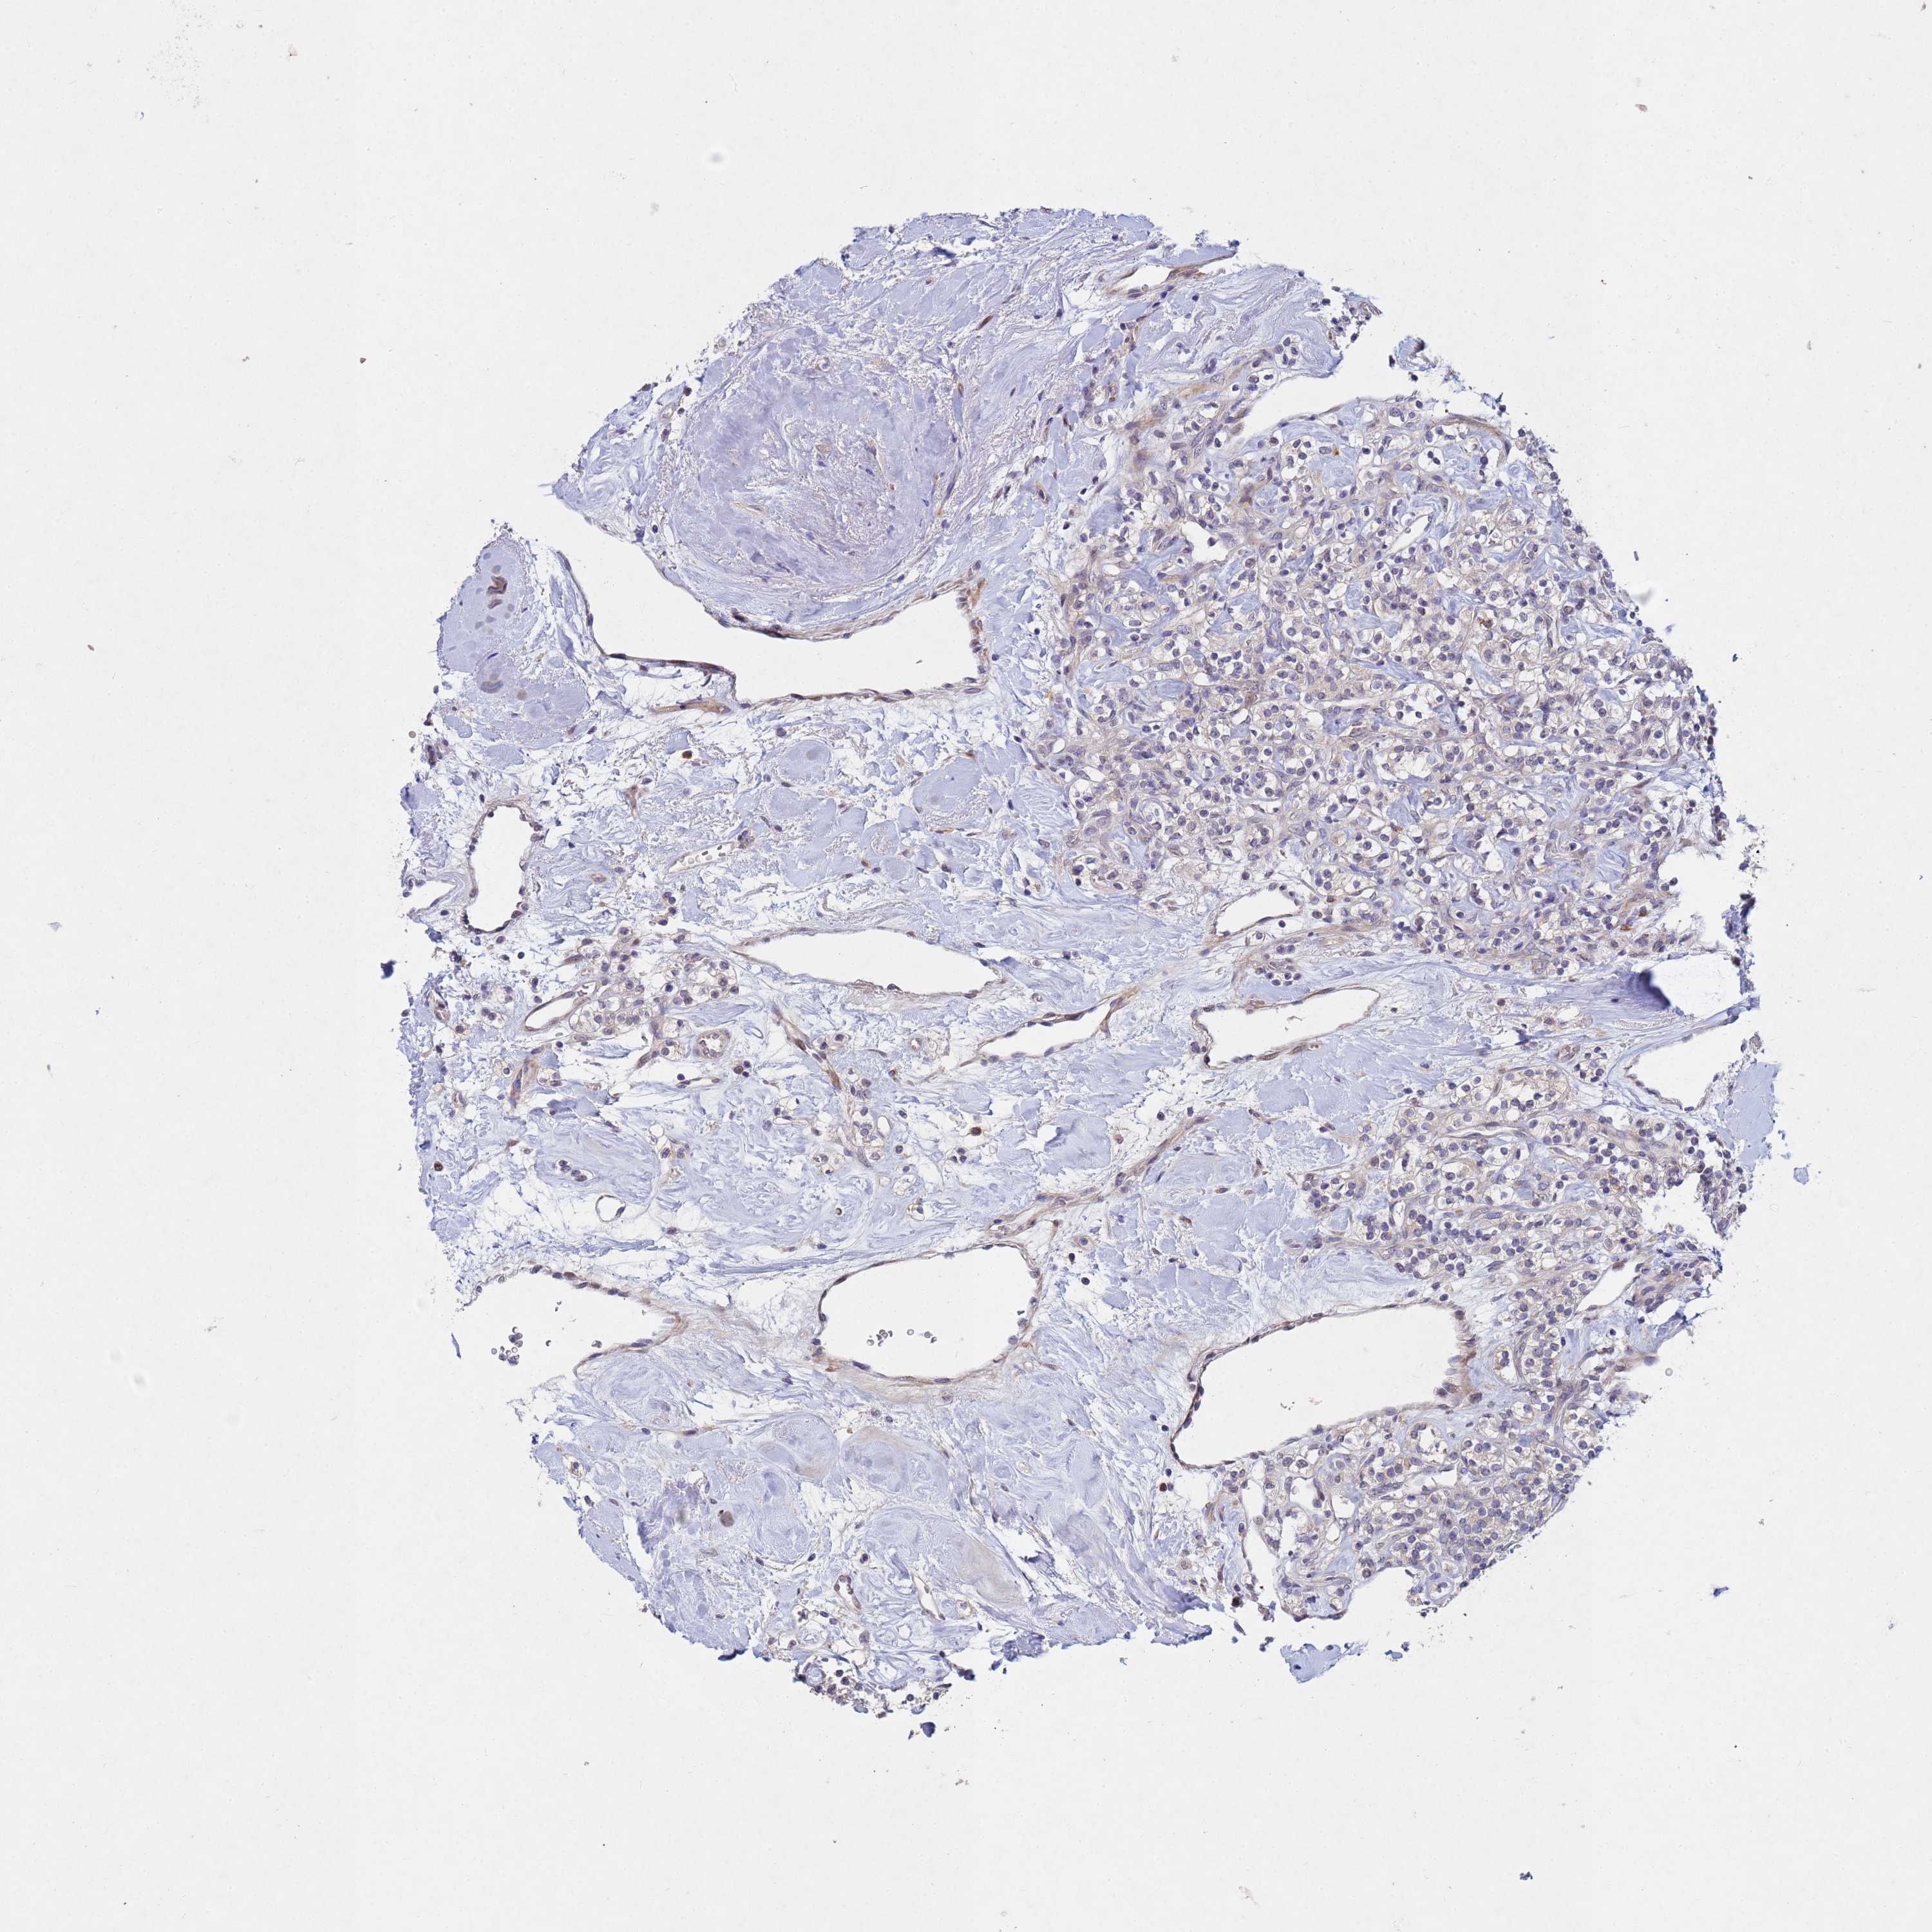

KIDNEY RENAL PAPILLARY CELL CARCINOMA (TCGA) - Interactive survival scatter ploti

The Survival Scatter plot shows the clinical status (i.e. dead or alive) for all individuals in the patient cohort, based on the same data that underlies the corresponding Kaplan-Meier plots. Patients that are alive at last time for follow-up are shown in blue and patients who have died during the study are shown in red.

The x-axis shows the expression levels (FPKM) of the investigated gene in the tumor tissue at the time of diagnosis. The y-axis shows the follow-up time after diagnosis (years). Both axes are complimented with kernel density curves demonstrating the data density over the axes. The top density plot shows the expression levels (FPKM) distribution among dead (red) and alive patients (blue). The right density plot shows the data density of the survived years of dead patients with high and low expression levels respectively, stratified using the cutoff indicated by the vertical dashed line through the Survival Scatter plot. This cutoff is automatically defined based on the FPKM cutoff that minimizes the p-score. The cutoff can be changed by dragging the vertical line or by entering a cutoff value in the square labeled "Current cut-off".

Under the Survival Scatter plot the p-score landscape (black curve; left axis) is shown together with dead median separation (red curve; right axis). Dead median separation is the difference in median mRNA expression between patients who have died with high and low expression, respectively. It is calculated as follows: median FPKM expression of dead patients with high expression - median FPKM expression of dead patients with low expression. This is intended to aid the user in visually exploring custom cutoffs and the associated p-scores and dead median separation.

Individual patient data is displayed and can be filtered by clicking on one or more of the category buttons on the top of the page. Categories describing expression level and patient information include: high, low, alive, dead, female, male and tumor stages. The scale of the x-axis can be toggled between linear and log-scale by clicking on the "x log" button. Mouse-over function shows TCGA ID, patient information and mRNA expression (FPKM) for each patient.

& Survival analysisi

Kaplan-Meier plots summarize results from analysis of correlation between mRNA expression level and patient survival. Patients were divided based on level of expression into one of the two groups "low" (under cut off) or "high" (over cut off). X-axis shows time for survival (years) and y-axis shows the probability of survival, where 1.0 corresponds to 100 percent.

TNPO2 is not prognostic in Kidney Renal Papillary Cell Carcinoma (TCGA)